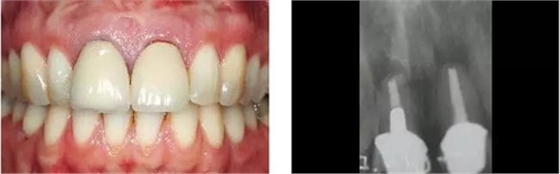

圖1、外形較大的雙側(cè)上中切牙唇側(cè)有瘺管,預(yù)后不佳,患者高笑線、薄齦生物型。

圖2、放射線片顯示雙側(cè)中切牙根尖均有感染病變。

圖14、最終修復(fù)體就位,冠頸部較窄。沒有任何牙齦和牙齦乳頭的退縮。

圖15、種植體植入后12個月的微笑相。